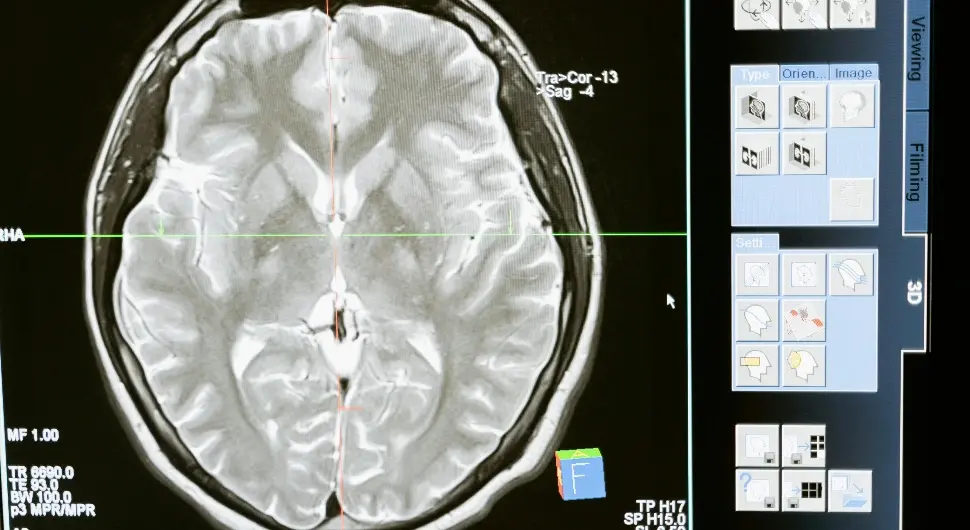

Оштећење мозга изазвано зачепљењем крвних судова можда би се у будућности могло лијечити ињекцијама матичних ћелија, показује нова студија истраживача са Универзитета у Цириху (University of Zurich) и Универзитета Јужне Калифорније (University of Southern California).

Овакве терапије би могле помоћи пацијентима који су доживјели одређене облике можданог удара да поврате изгубљене функције, пише Сајенс Алерт (Science Alert).

Користећи мишеве са оштећењем мозга изазваним можданим ударом, истраживачи су открили да ињекције људских матичних ћелија могу успјешно да се развију у младе мождане ћелије. Резултати су били изузетни – већина усађених ћелија остала је на мјесту, развивши особине потпуно функционалних неурона и комуницирајући са околним ћелијама.

Тренутно је оштећење мозга изазвано можданим ударом неповратно. Унутрашње крварење или недостатак кисеоника који настају услед удара трајно уништавају мождане ћелије, што може значајно утицати на говор и покрете.